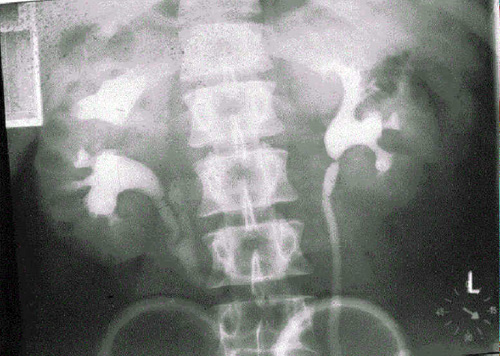

Антеградная цистография: медицинские исследования и примеры